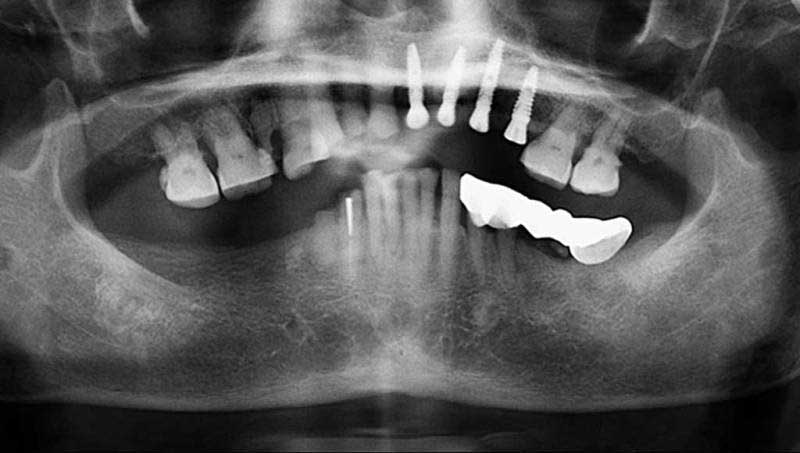

案例4